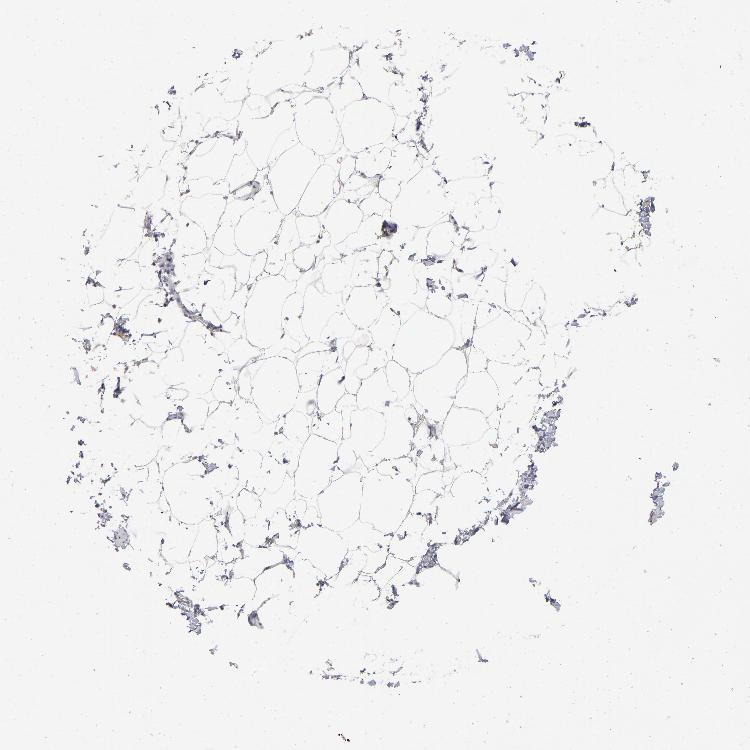

ADIPOSE TISSUE - Antibody stainingi

Antibody staining in the annotated cell types in the current human tissue is reported as not detected, low, medium, or high, based on conventional immunohistochemistry profiling in selected tissues. This score is based on the combination of the staining intensity and fraction of stained cells.

Each image is clickable and will lead to virtual microscopy that enables deeper exploration of all samples and also displays staining intensity scores, fraction scores and subcellular localization as well as patient and tissue information for each sample.

Antibody HPA003595Antibody HPA024006Antibody CAB009434Antibody CAB056159Antibody CAB080011

Adipocytes Not detectedNot detectedLowNot detectedNot detected